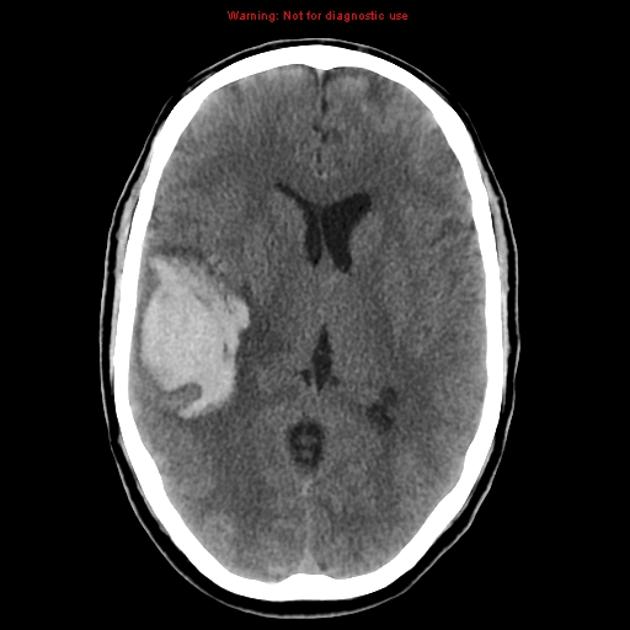

CT brainAVM non-contrast hematoma.

Hematoma Comparison.

Ct-scan of the brain with an subdural hematoma.